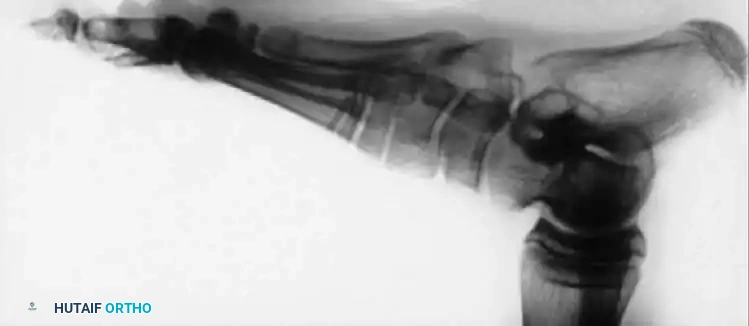

Arthrodesis of the Foot:

In adults or older adolescents with fixed, static deformities, tendon transfers alone are insufficient. The Triple Arthrodesis (fusion of the subtalar, calcaneocuboid, and talonavicular joints) is the definitive procedure for stabilizing a flail hindfoot and midfoot.

Image

Surgical Warning: In growing children, bony procedures should be delayed until skeletal maturity (typically >12 years of age) to prevent severe growth arrest and secondary deformities. Extra-articular subtalar arthrodesis (Grice-Green procedure) can be utilized in younger children to stabilize the hindfoot without violating the physes.